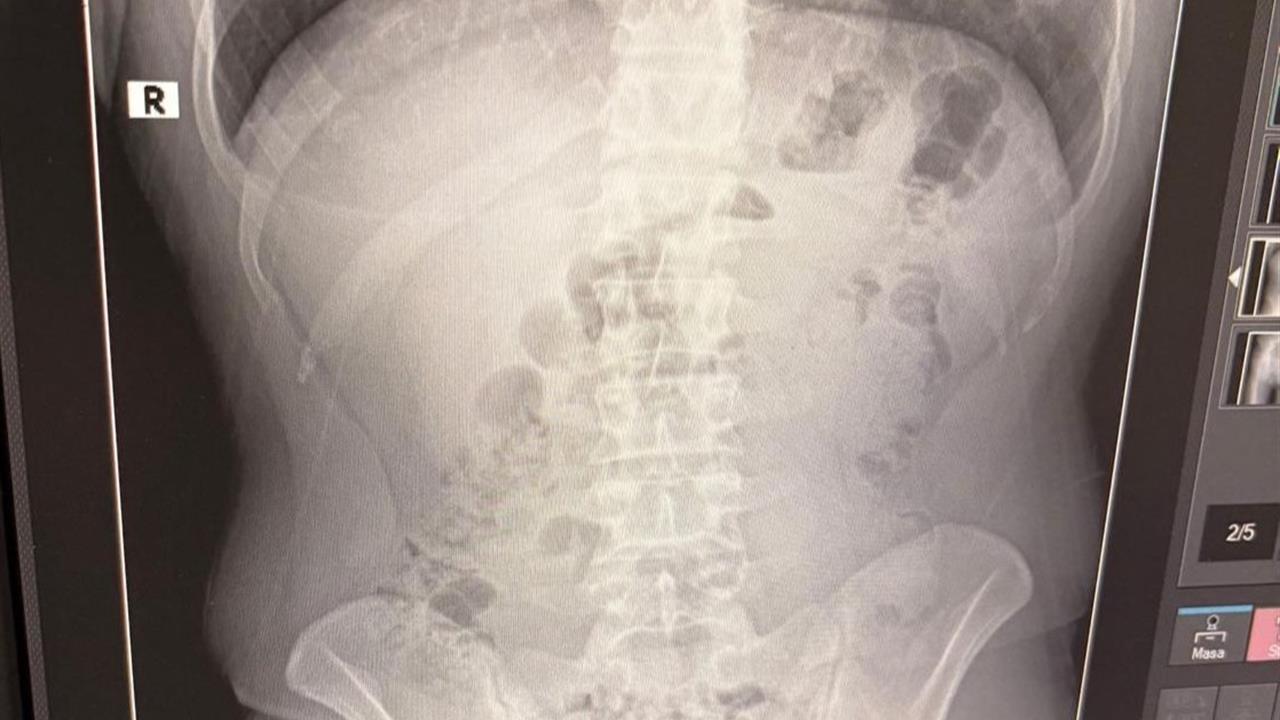

Adreste yapılan aramada, şüphelilerden birinin üstünde 1 kapsül bulundu. Şüphe üzerine hastaneye götürülen şahısların midelerinde de kapsül içinde metamfetamin tespit edildi. Hastanede tedavi altına alınan şüphelilerin vücudundan çıkarılan kapsüllerle birlikte toplamda 1 kilo 516 gram metamfetamin ele geçirildi. Ele geçirilen uyuşturucu maddelere el konulurken, şüpheliler emniyetteki işlemlerinin ardından adliyeye sevk edildi. Çıkarıldıkları mahkemece tutuklanan Y.T., A.T. ve M.J. cezaevine gönderildi.